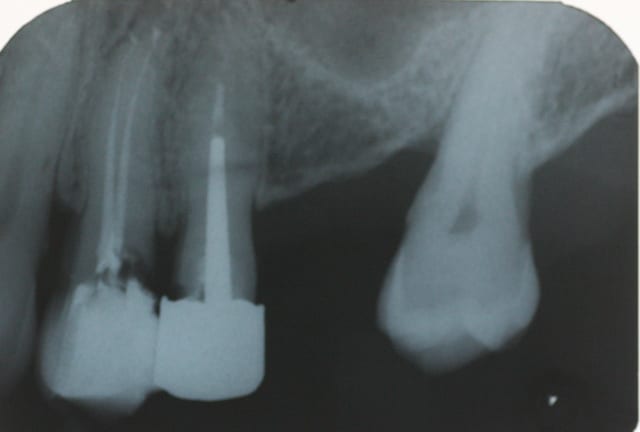

pour relancer le débat, dans un cas comme ça vous faites quoi?

- bridge? avec 27 vivante?

- sinus + implant ? coronoplastie de la 27 pour redresser l'axe ?

- stellite une dent?

- obiwan kenobi?

la radio...